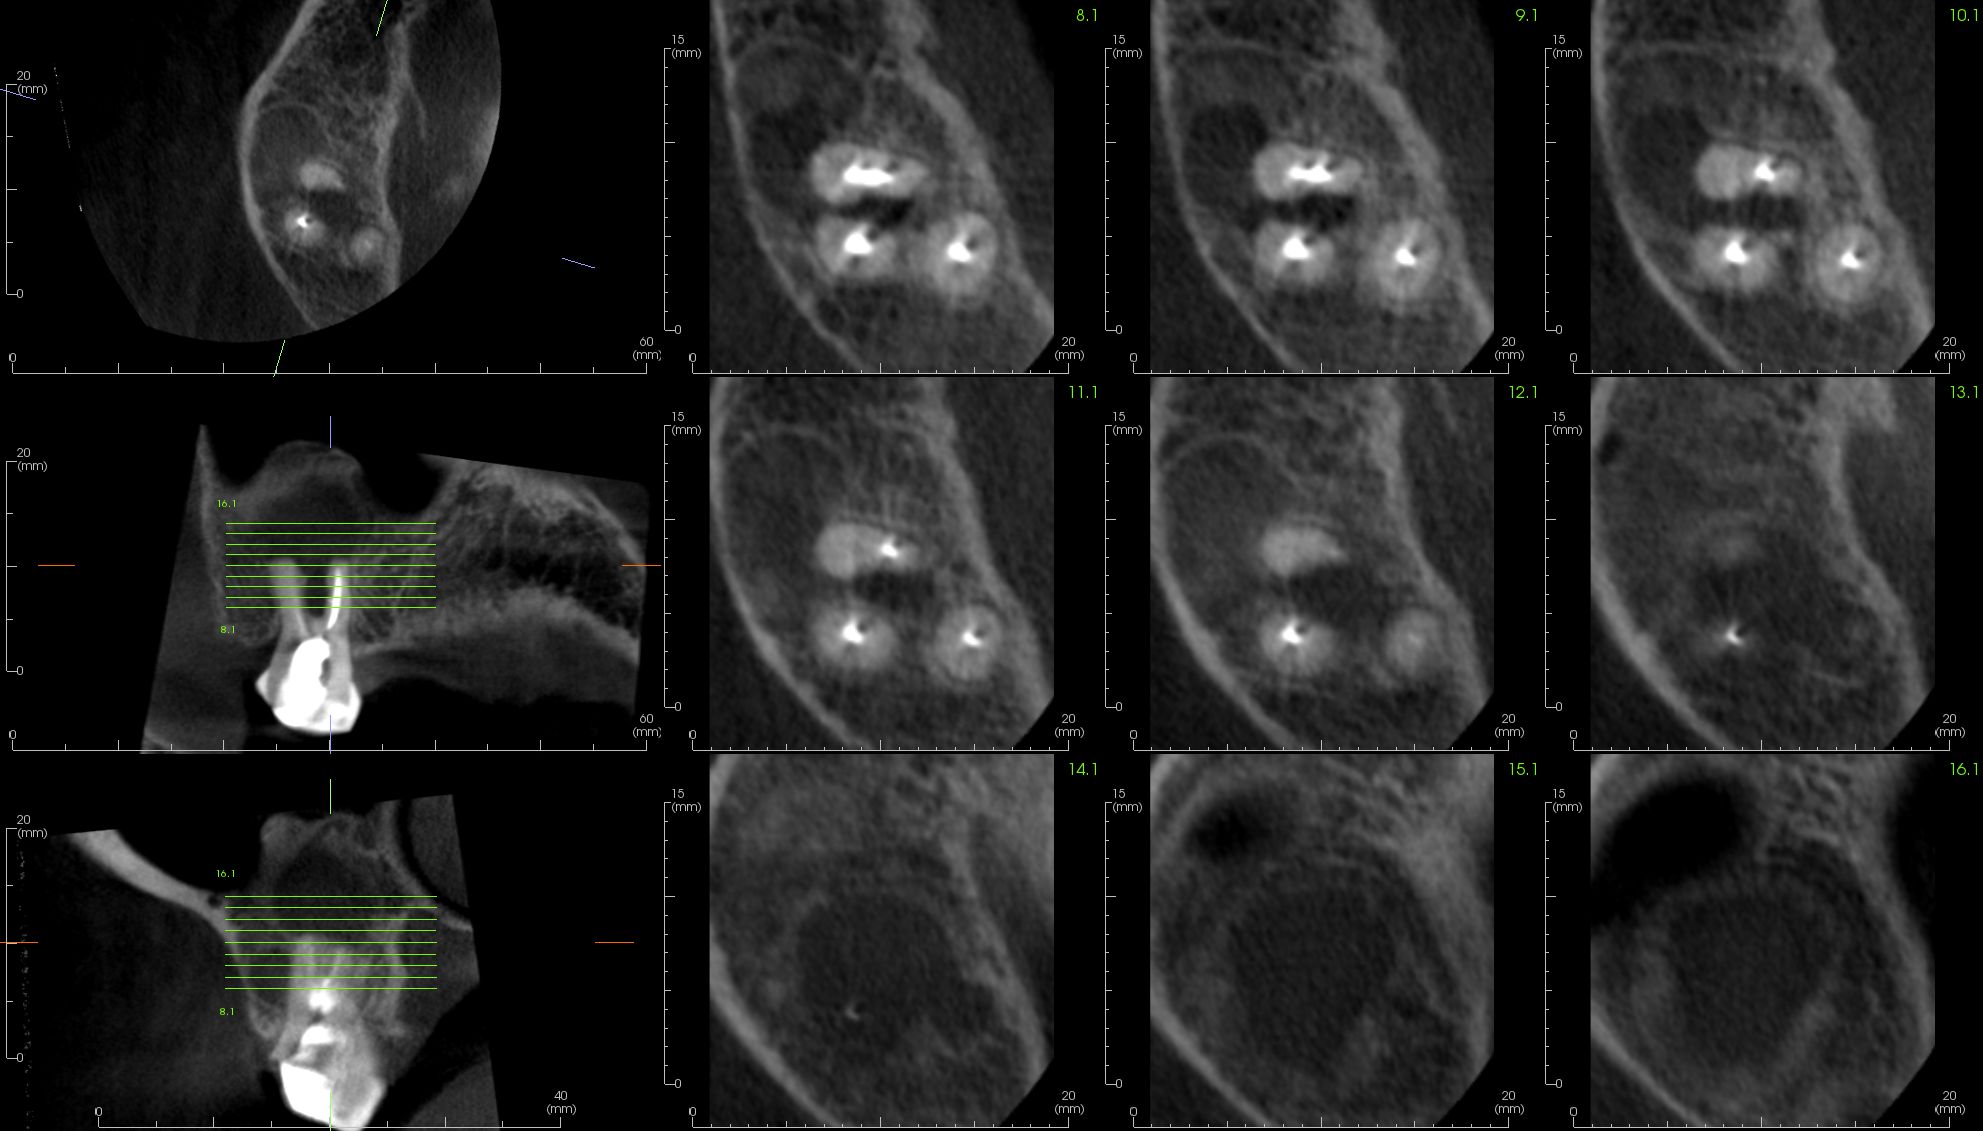

Image Portfolios visually communicate the imaging goals to you and your patient.